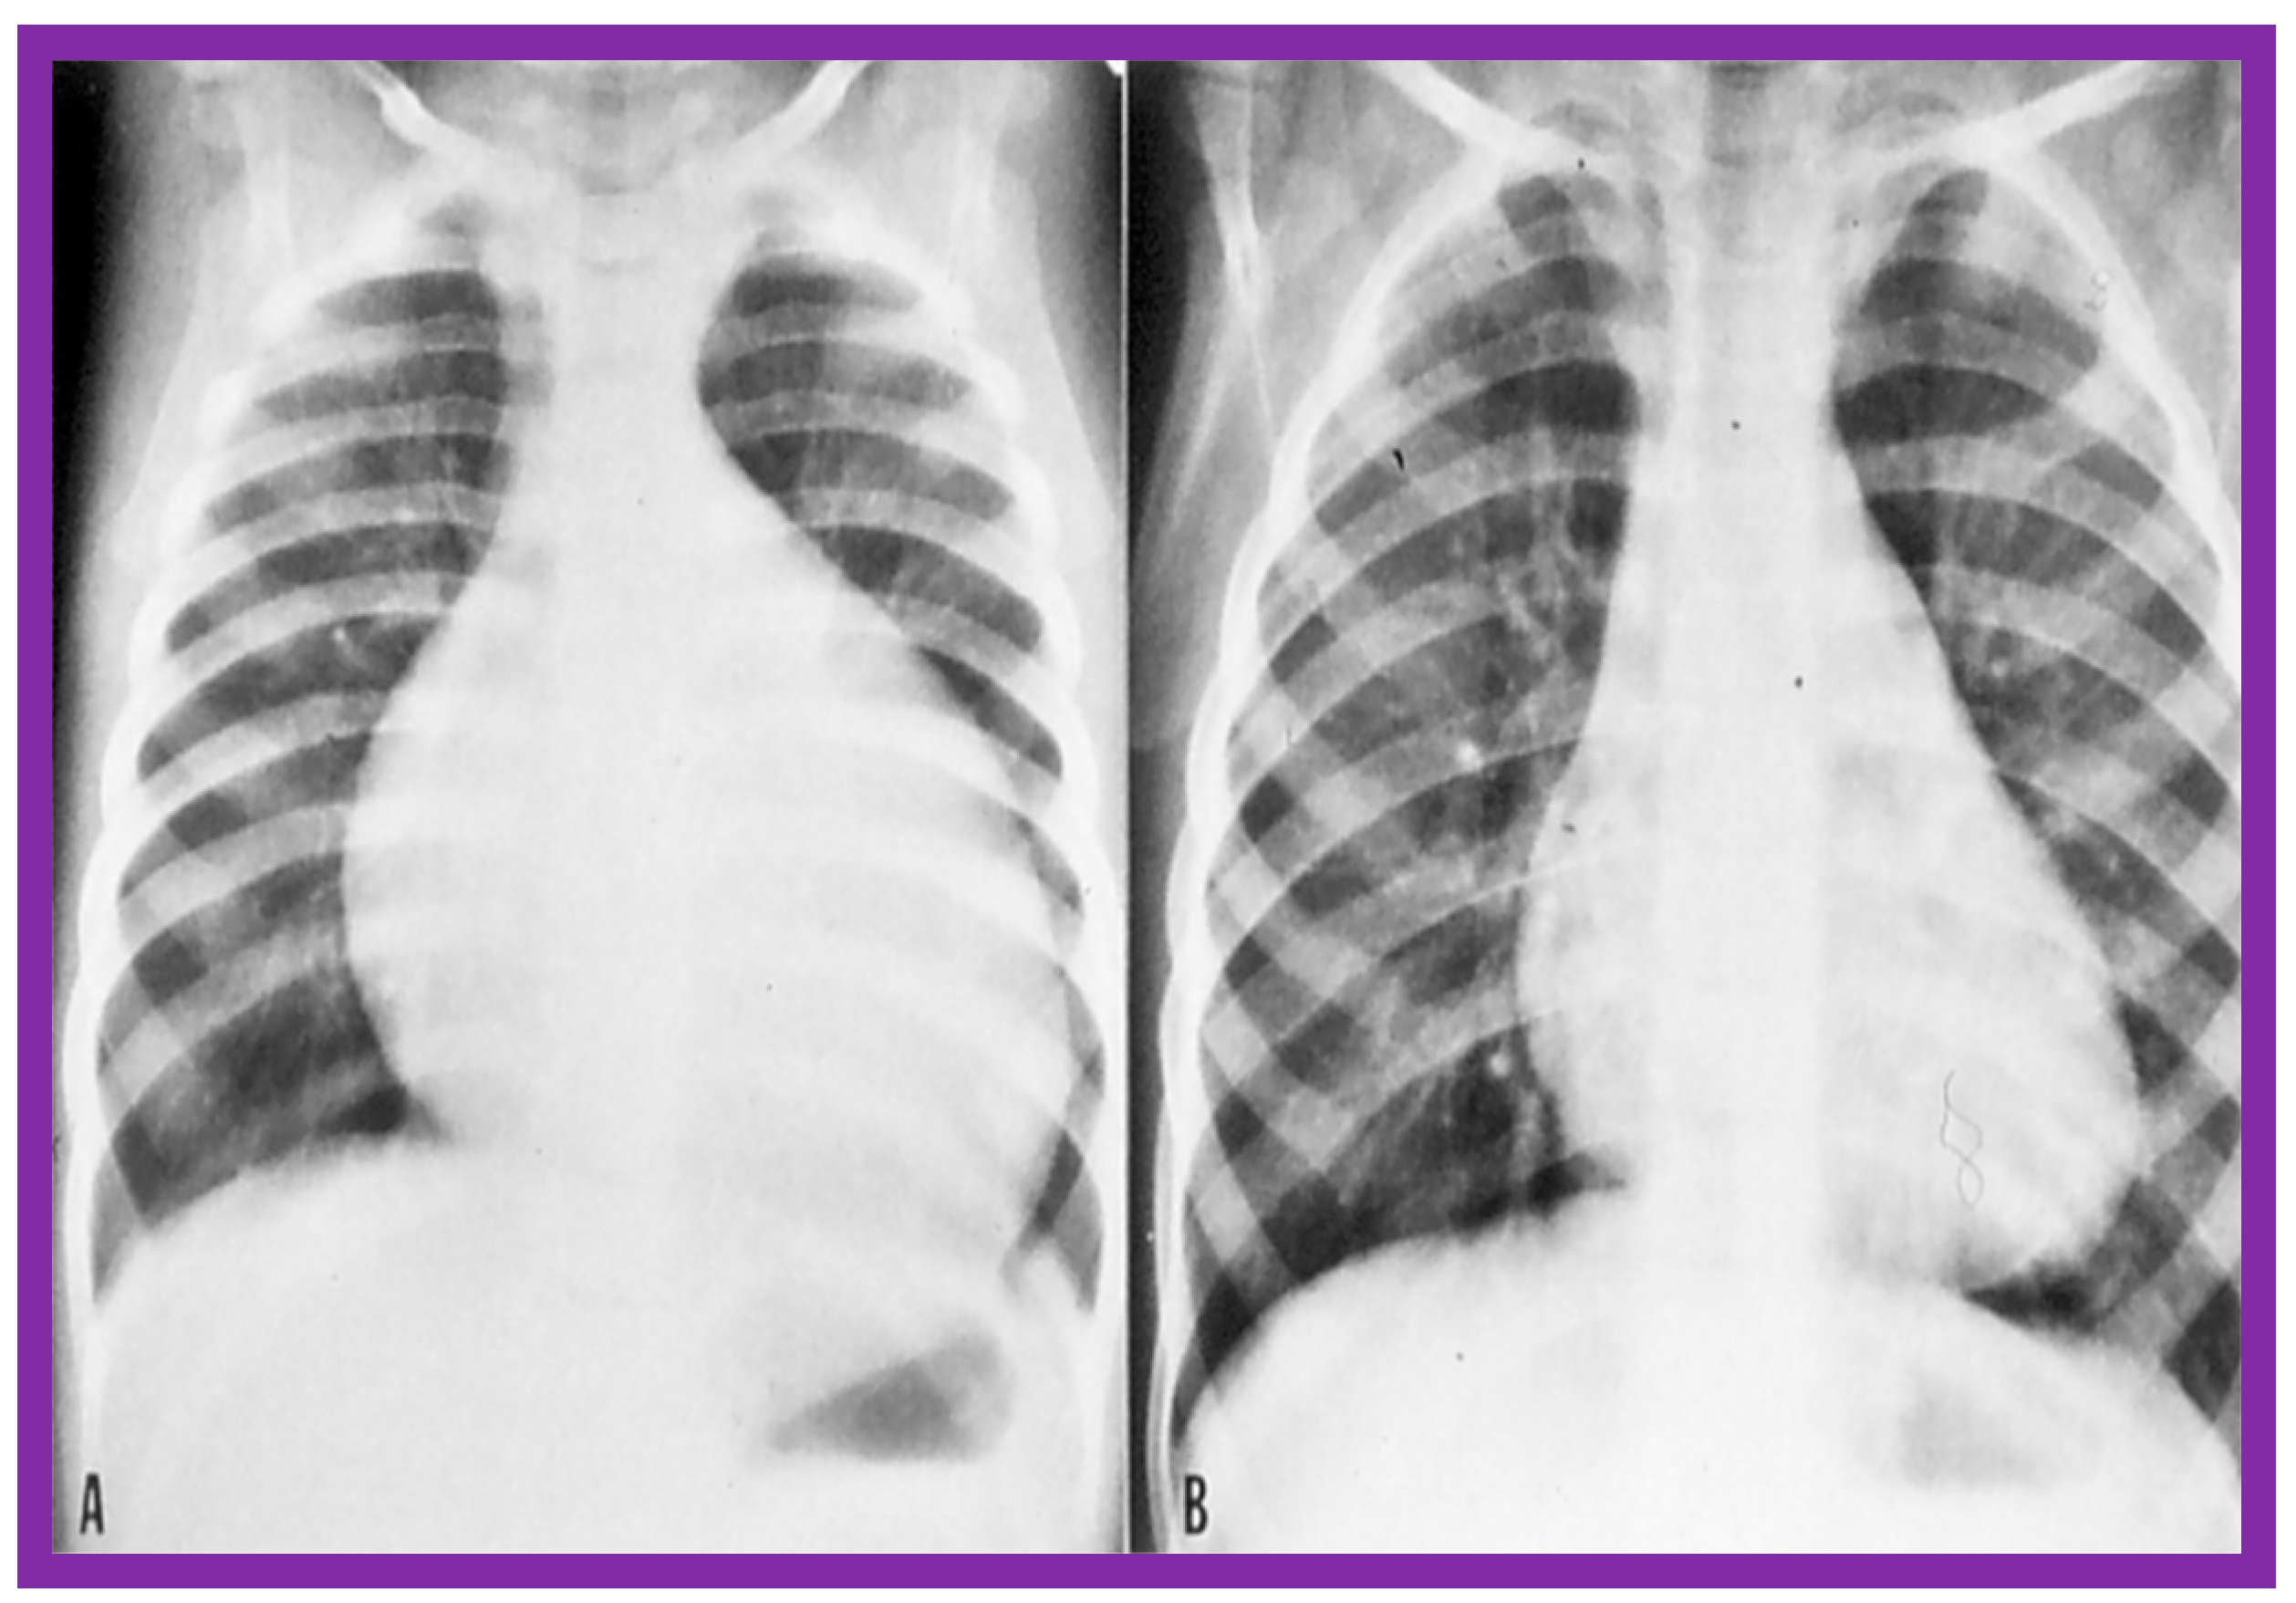

- Rao, P.S.; Najjar, H.N.; Mardini, M.K.; Solymar, L.; Thapar, M.K. Balloon angioplasty for coarctation of the aorta: Immediate and long-term results. Am. Heart J. 1988, 115, 657–665. [Google Scholar] [CrossRef]